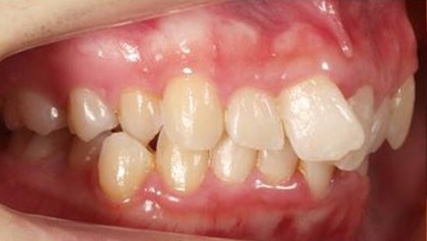

治療前

治療終了前

前歯が咬んでいない状態を言います。受け口同様、奥歯への負担が大きく、歯を失いやすい不正咬合と言われております。インビザラインでの治療の方が、ワイヤーを用いた治療より治療しやすい症例が多く、治療期間はワイヤー治療に比べて比較的短期間になることが多いです。出っ歯、同じように口呼吸、舌の位置が悪い、口が閉じれないなどの症状を伴うことが多いので、そういった点も考慮して治療していく必要があります。